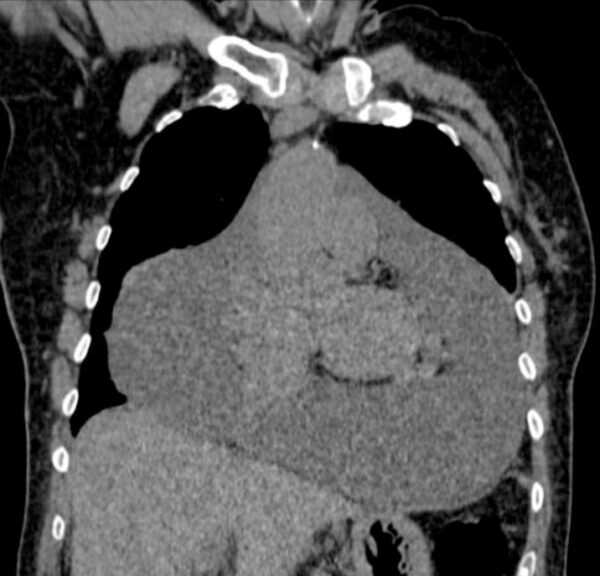

Case 21

https://radiopaedia.org/cases/pericardial-effusion-large-2

CT

CVS